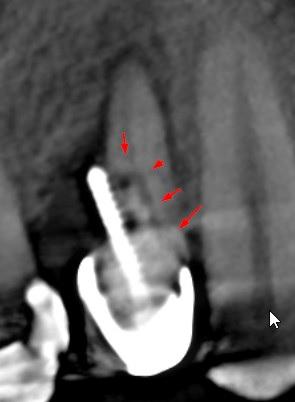

Ząb 24 nosi znamiona leczenia endodontycznego.

Uwidoczniono perforacją korzenia policzkowego wkładem koronowo – korzeniowym.

Perforacja występuje na ścianie dystalnej korzenia - zmiana osteolityczna w kości w projekcji perforacji.

W strukturze korzeni widoczna szczelna pęknięcia.